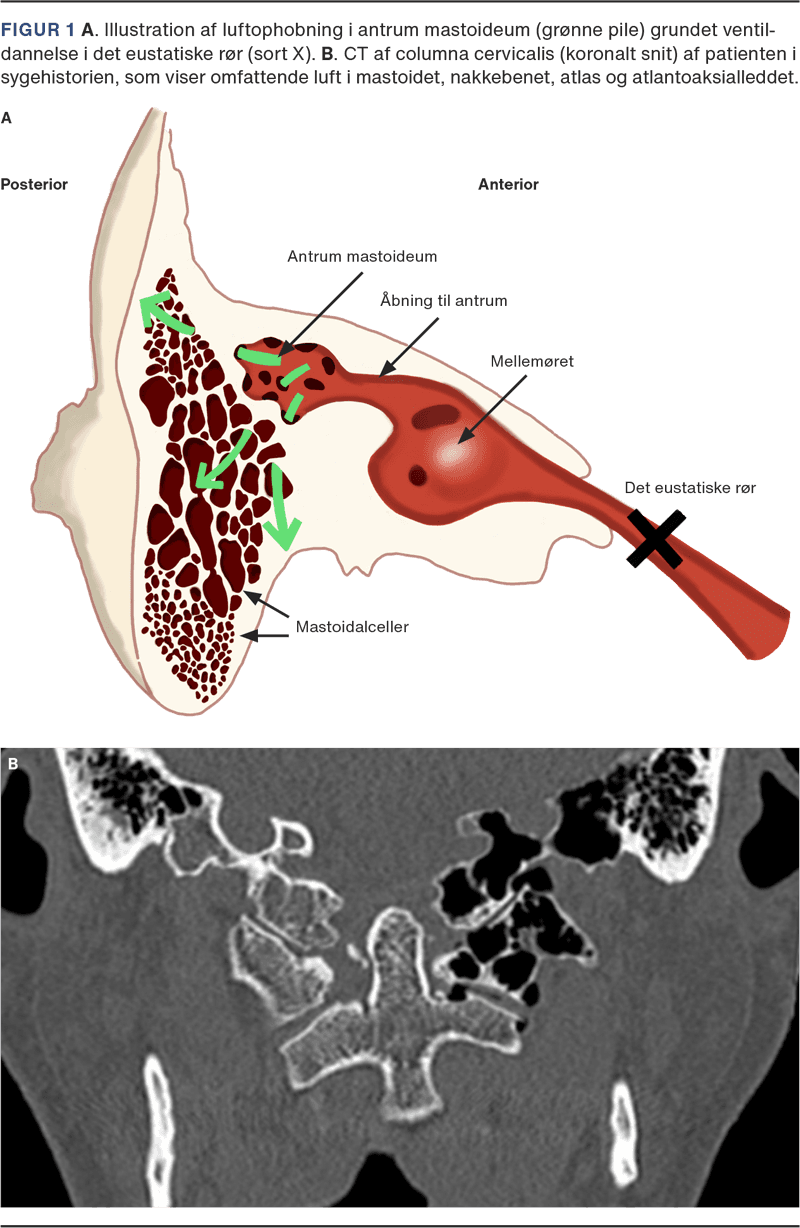

Kraniocervikal pneumatisering er en yderst sjælden tilstand med få beskrevne tilfælde på verdensplan [1]. Tilstanden er karakteriseret ved en gradvis fortrængning af knoglevæv til fordel for luft i nakkebenet og i de øverste nakkehvirvler. Årsagen er ikke entydigt klarlagt, men hyppigst rapporteres ventildannelse i det eustakiske rør som en mulig årsag [1]. Idet luften ophobes i mellemøret, vil den penetrere og dissekere sig ind i knoglevævet omkring mastoidet (Figur 1 A), videre ind i nakkebenet og sjældent videre til de øverste halshvirvler. Mulige udløsere for denne ventildannelse formodes at være hyppig Valsalvas manøvre, kraftig og gentagen hoste, hyppige ophold i store højder, medfødte misdannelser eller tidligere kirurgiske indgreb i mellemøret. Over tid kan knoglevævet gradvist blive fortrængt og udtyndet med øget risiko for fraktur. Vi rapporterer i denne kasuistik om et tilfælde af tilfældigt opdaget kraniocervikal pneumatisering efter et mindre traume.

Ved opfølgning var patientens gener forsvundet, og den objektive undersøgelse var upåfaldende. En opfølgende CT viste uændret pneumatisering uden tegn på fraktur (Figur 1 B). Gennemgang af tidligere billeddiagnostisk materiale (CT af cerebrum grundet traume i 2016 og 2023) viste begge kraniocervikal pneumatisering, som var tiltaget gradvist over tid. Anamnese afslørede hyppige mellemøreinfektioner i barndommen samt tidligere operation i mellemøret grundet stigbøjle/ambolt-fiksation – en mulig årsag til pneumatiseringen. På baggrund af den langvarige historik og fraværet af fraktur blev der valgt en konservativ strategi: seponering af halskrave, vejledning om at undgå overdrevne Valsalvas manøvrer samt klinisk opfølgning.